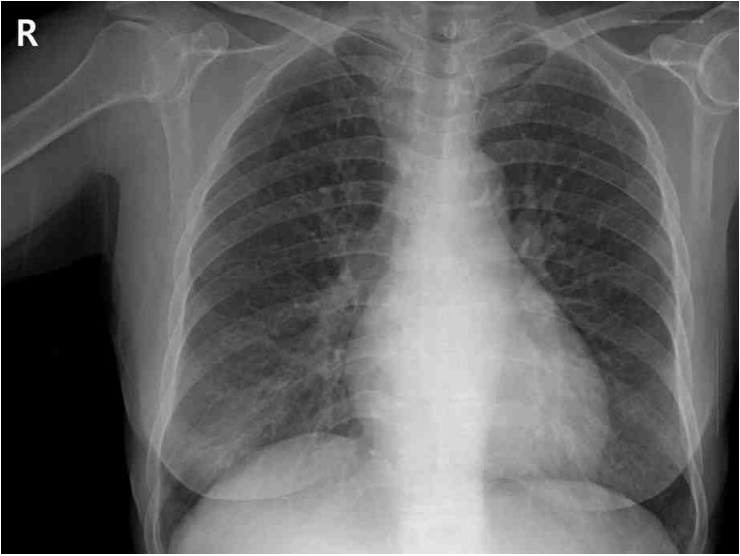

75세 여자가 3시간 전부터 숨이 찬다며 병원에 왔다. 5일 전 왼쪽 고관절 골절로 수술을 받았다고 한다. 5년 전부터 경구 혈당강하제를 복용 중이고 비흡연자이다. 혈압 120/70 mmHg, 맥박 110회/분, 호흡 26회/분, 체온 36.5°C이다. 호흡음은 정상으로 들린다. 왼쪽 종아리 부위가 오른쪽에 비해 부어있다. 맥박산소측정 시 산소포화도는 90%이다. 가슴 X선사진이다. 혈액검사 결과는 다음과 같다. 검사는?

CXR: No remarkable findings

• 현재 V/S stable하고 CXR에서 특이소견 관찰되지 않으나 왼쪽 종아리가 오른쪽에 비해 부어있으며, immobilization 상태를 고려할 때 DVT가 강력하게 의심되며 이로 인한 PTE에 대한 감별이 필요하다.